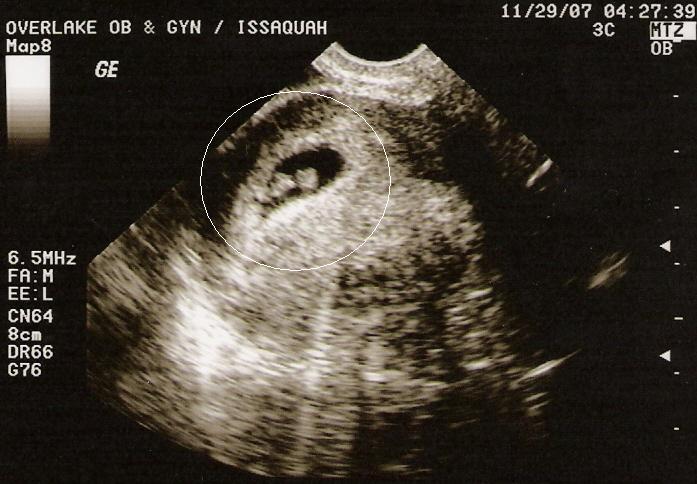

First Ultrasound

We had our first ultrasound today. It was awesome! We got to see the little heart beating away. Sometimes the picture was so clear Jim saw the two flaps of the heart beating one after another. I can’t describe the feeling of seeing that tiny being living inside me. We are reminded of God’s amazing creation. We get to go in tomorrow for another ultrasound to specifically measure the baby and get a more accurate estimated due date.

You can see the miniature lima-bean of a baby inside the black tear drop. I circled it just in case you’re wondering. 🙂 Jim voted on this picture (we have four) because you can most clearly see the head (top right) and the bottom of the body (lower left).